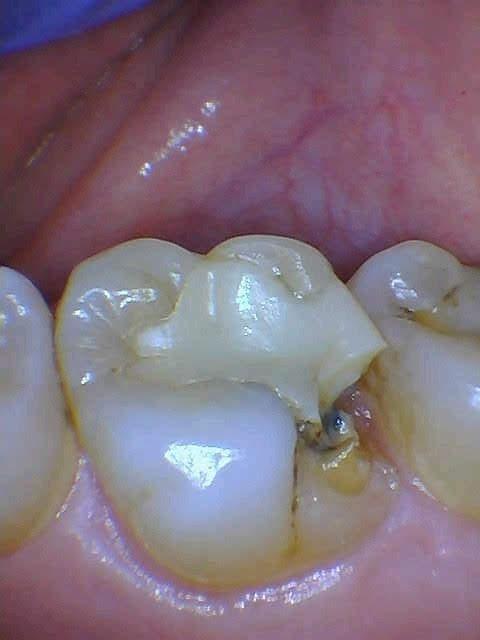

Cusp fractured off upper molar, fixed with same day crown.

Before

After